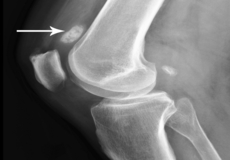

Osteochondritis Dissecans of the Knee

Osteochondritis dissecans is a joint condition in which a piece of cartilage, along with a thin layer of the bone separates from the end of the bone because of inadequate blood supply. The separated fragments are sometimes called “joint mice”. These fragments may be localized or may detach and fall into the joint space, causing pain and joint instability.

Osteochondral Defect of the Knee

An osteochondral defect, also commonly known as osteochondritis dissecans, of the knee refers to a damage or injury to the smooth articular cartilage surrounding the knee joint and the bone underneath the cartilage. The degree of damage may range from a rupture of the cartilage to a slight crack of the bone to a piece of the bone breaking off within the joint.